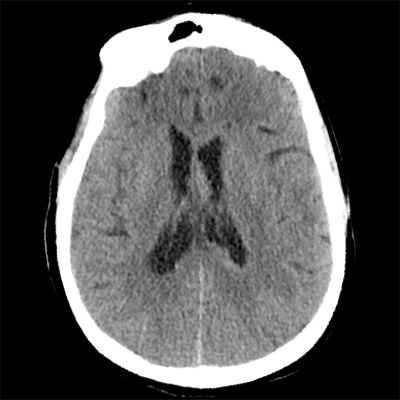

You arrive at the patient's room. You quickly examine her. Her left pupil is truly dilated and unreactive. Her right pupil is also dilated and unreactive, and also deviates to the right. She is unable to follow commands but is moving her extremities spontaneously. The right side of her body seems to be moving slightly less than her left. You escort the patient with RRT and your neurology colleague to radiology, where a non-contrast head CT and CTA head/neck are obtained.

HCT part 1 HCT part 2 HCT part 3

The non-contrast head CT looks generally similar to her prior scan. There's no new hemorrhage anywhere. There's no mass effect causing midbrain compression. The vessel imaging also looks unrevealing-- a slightly hypoplastic right A1 segment, but no clear LVO in either the anterior or posterior circulation. There's no vasoconstriction.